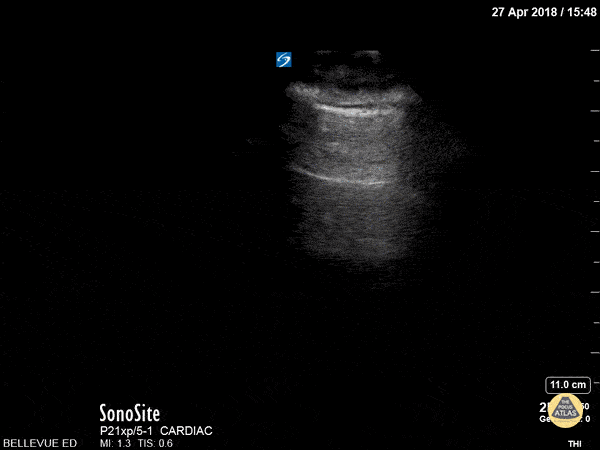

Lung Sliding and a-lines This is a clip demonstrating lung sliding. The most superficial hyperechoic layers are the soft tissue and muscular layers of the chest wall. Immediately deep to that is a bright, thin hyperechoic line which appears to be in motion - this is the pleural line. The parietal pleura rubbing against the visceral pleura as the patient breathes creates this shimmery appearance of lung sliding also often described as “ants marching”. The next horizontal hyperechoic line deep to the pleura is an a-line; this is a reverberation artifact created by a reflection of the pleura. The presence of a-lines is a normal finding.